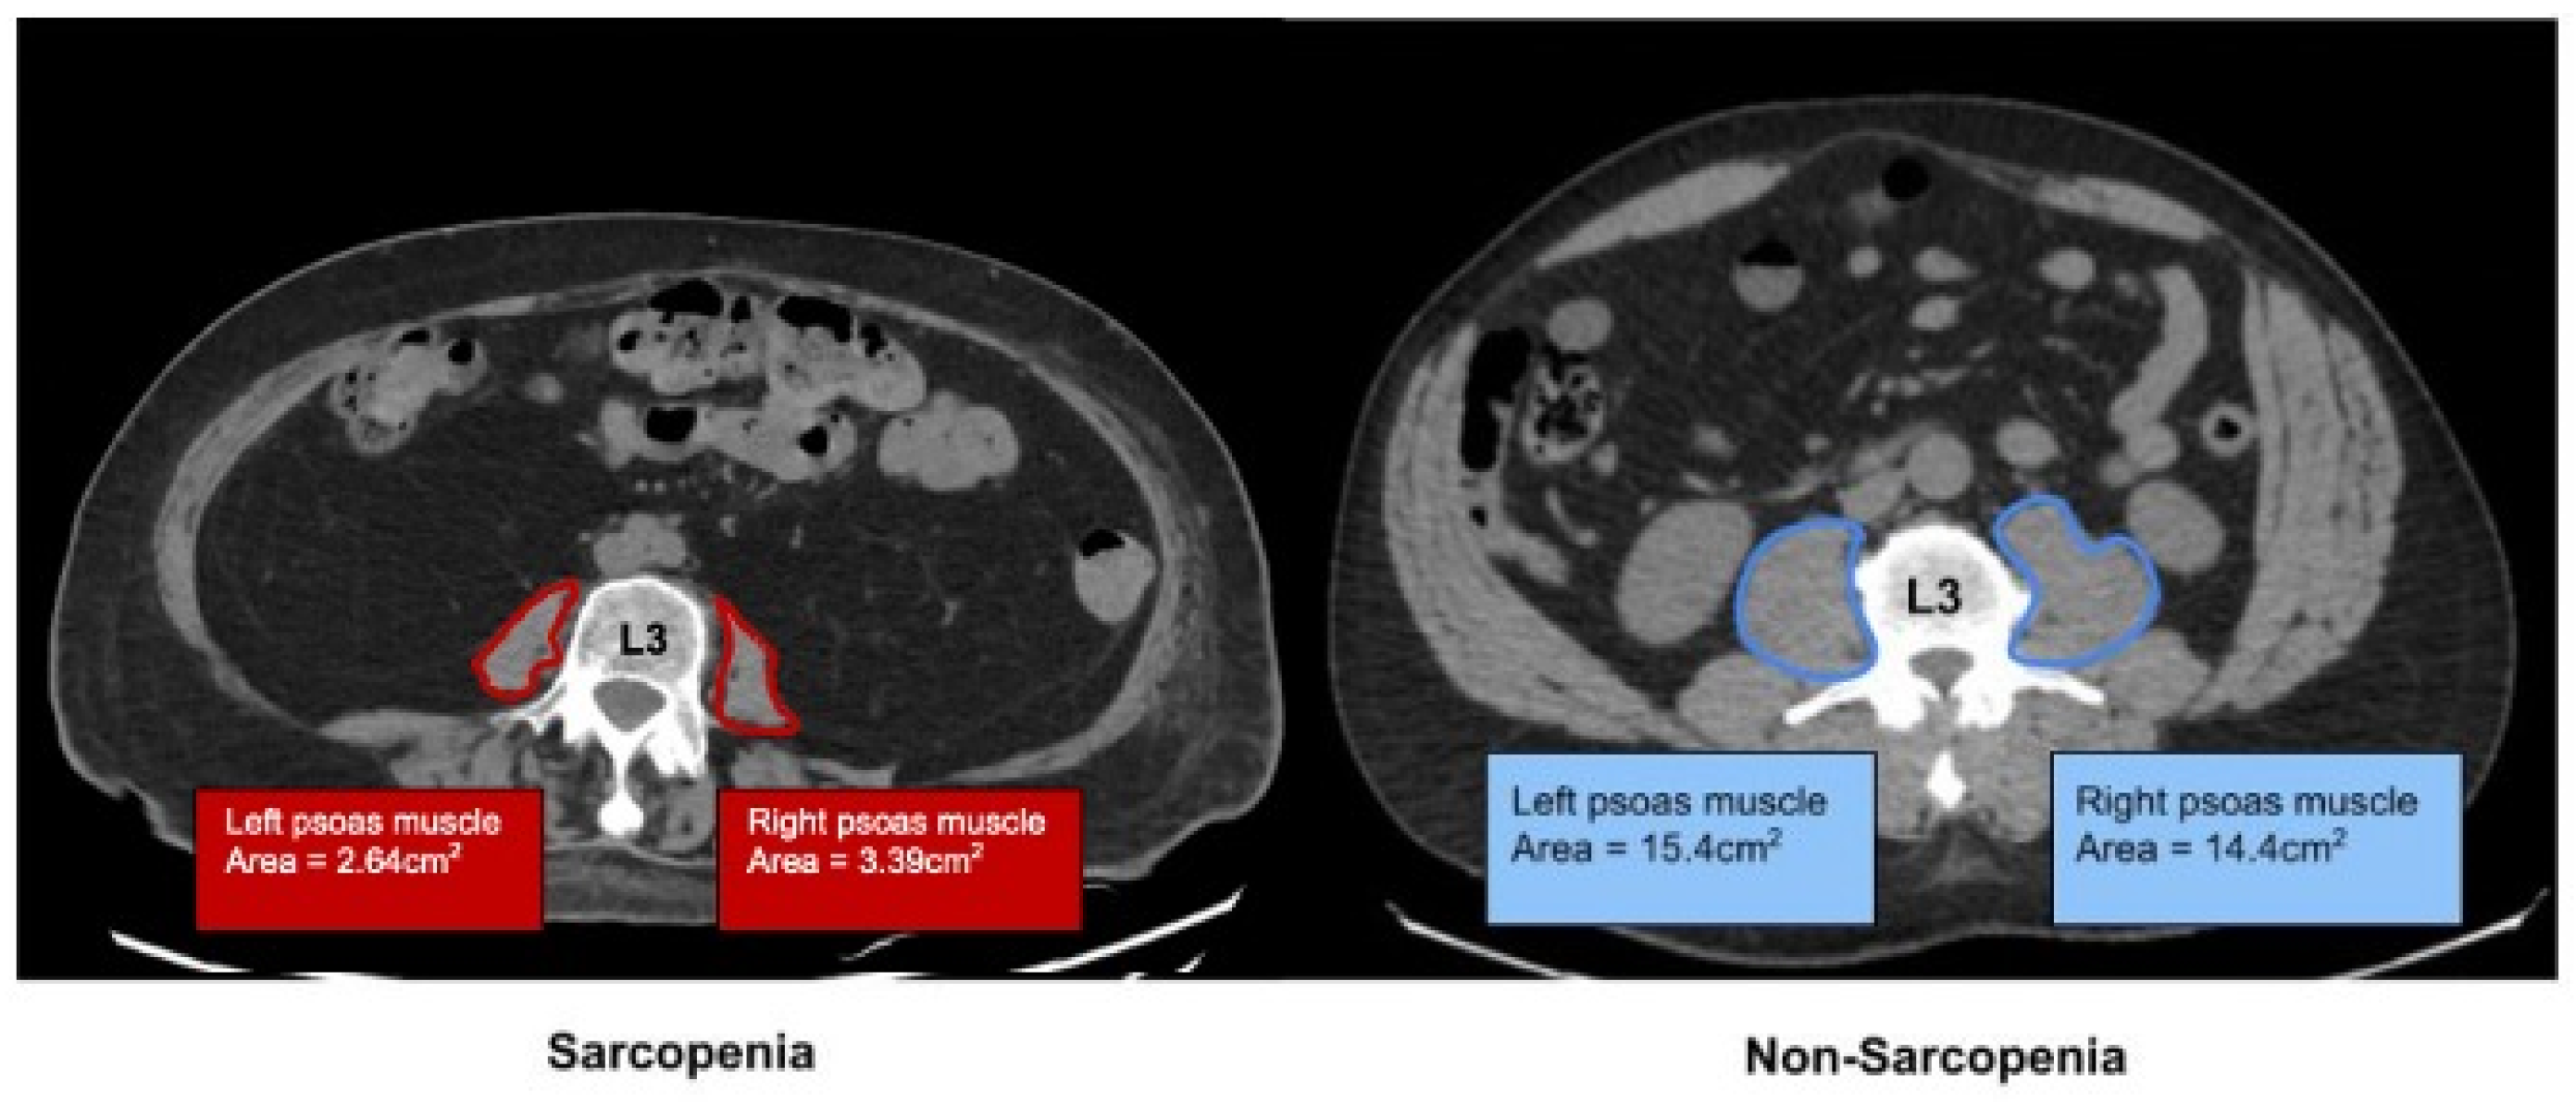

2.1. Determination of Sarcopenia by Imaging

- Bahat, G.; Turkmen, B.O.; Aliyev, S.; Catikkas, N.M.; Bakir, B.; Karan, M.A. Cut-off values of skeletal muscle index and psoas muscle index at L3 vertebra level by computerized tomography to assess low muscle mass. Clin. Nutr. 2021, 40, 4360–4365. [Google Scholar] [CrossRef]